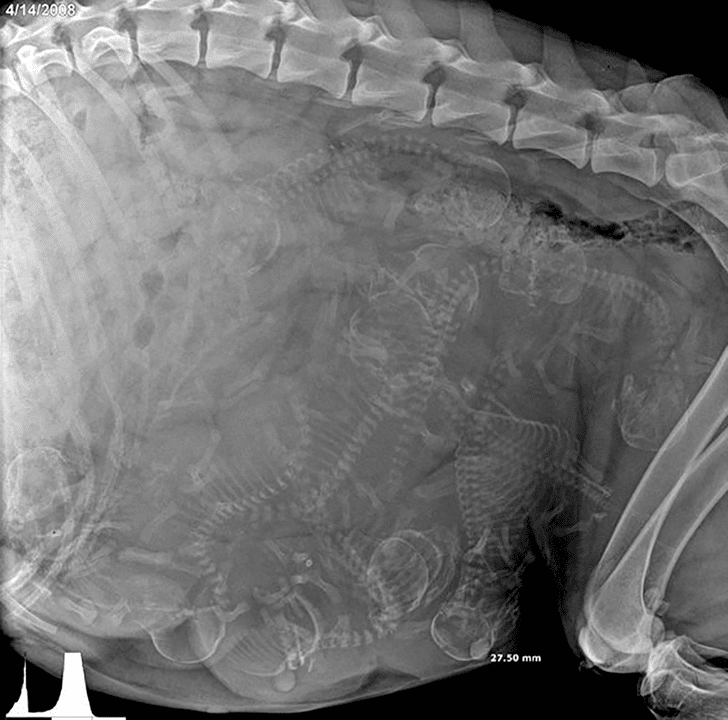

7. Radiografía de una perrita embarazada

¿Cuántos cachorros puedes contar?